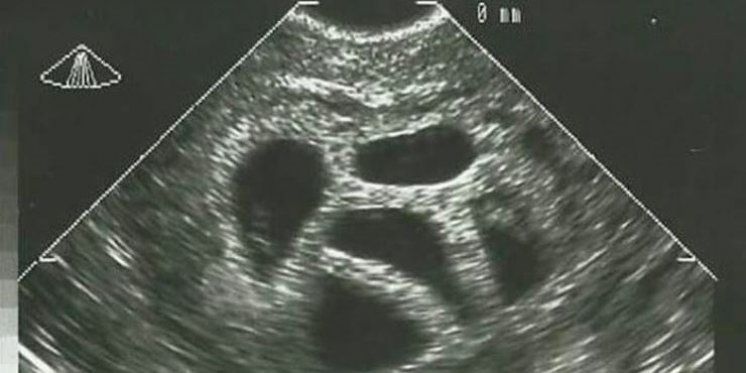

“U dobi od 28 godina saznala sam da sam trudna i to s petorkama. Moj liječnik odmah mi savjetovao selektivni pobačaj, prenosi Narod hr.